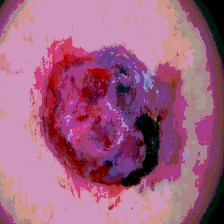

Timely identification and treatment of rapidly progressing skin cancers can significantly contribute to the preservation of patients' health and well-being. Dermoscopy, a dependable and accessible tool, plays a pivotal role in the initial stages of skin cancer detection. Consequently, the effective processing of digital dermoscopy images holds significant importance in elevating the accuracy of skin cancer diagnoses. Multilevel thresholding is a key tool in medical imaging that extracts objects within the image to facilitate its analysis. In this paper, an enhanced version of the Mud Ring Algorithm hybridized with the Whale Optimization Algorithm, named WMRA, is proposed. The proposed approach utilizes bubble-net attack and mud ring strategy to overcome stagnation in local optima and obtain optimal thresholds. The experimental results show that WMRA is powerful against a cluster of recent methods in terms of fitness, Peak Signal to Noise Ratio (PSNR), and Mean Square Error (MSE).